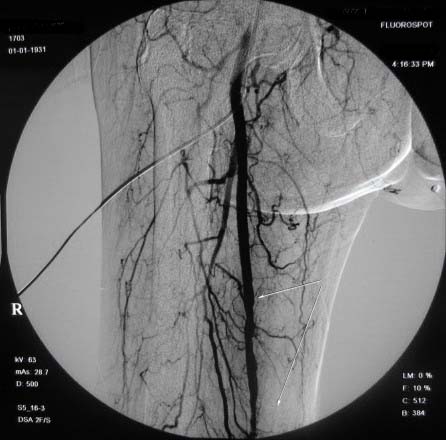

右下肢:

造影方法:取仰卧位,在局麻下,经右股动脉入路,采用改良seldingers技术,置入5f cobra导管于左髂外动脉行dsa,采集速度为2幅/秒,注射速率为6ml/秒,分节段造影;再将导管采用成襻技术放置于右侧髂外动脉,采用左侧同样的方法行dsa,术毕拔管、压迫止血约15分钟,包扎后嘱返病房,术后右足背动脉可扪及搏动。

右侧股浅动脉上、中段多处狭窄,下段闭塞。左侧股浅动脉多处狭窄,国动脉起始部狭窄。可以用球囊扩张配合动脉内溶栓或股浅动脉支架置入。多为糖尿病所致。

双侧股动脉及腘动脉多发狭窄,右股动脉下段闭塞并侧支形成。病变较广泛,球囊可试试,如病人经济不好,最好还是以药物治疗为主。个人意见。